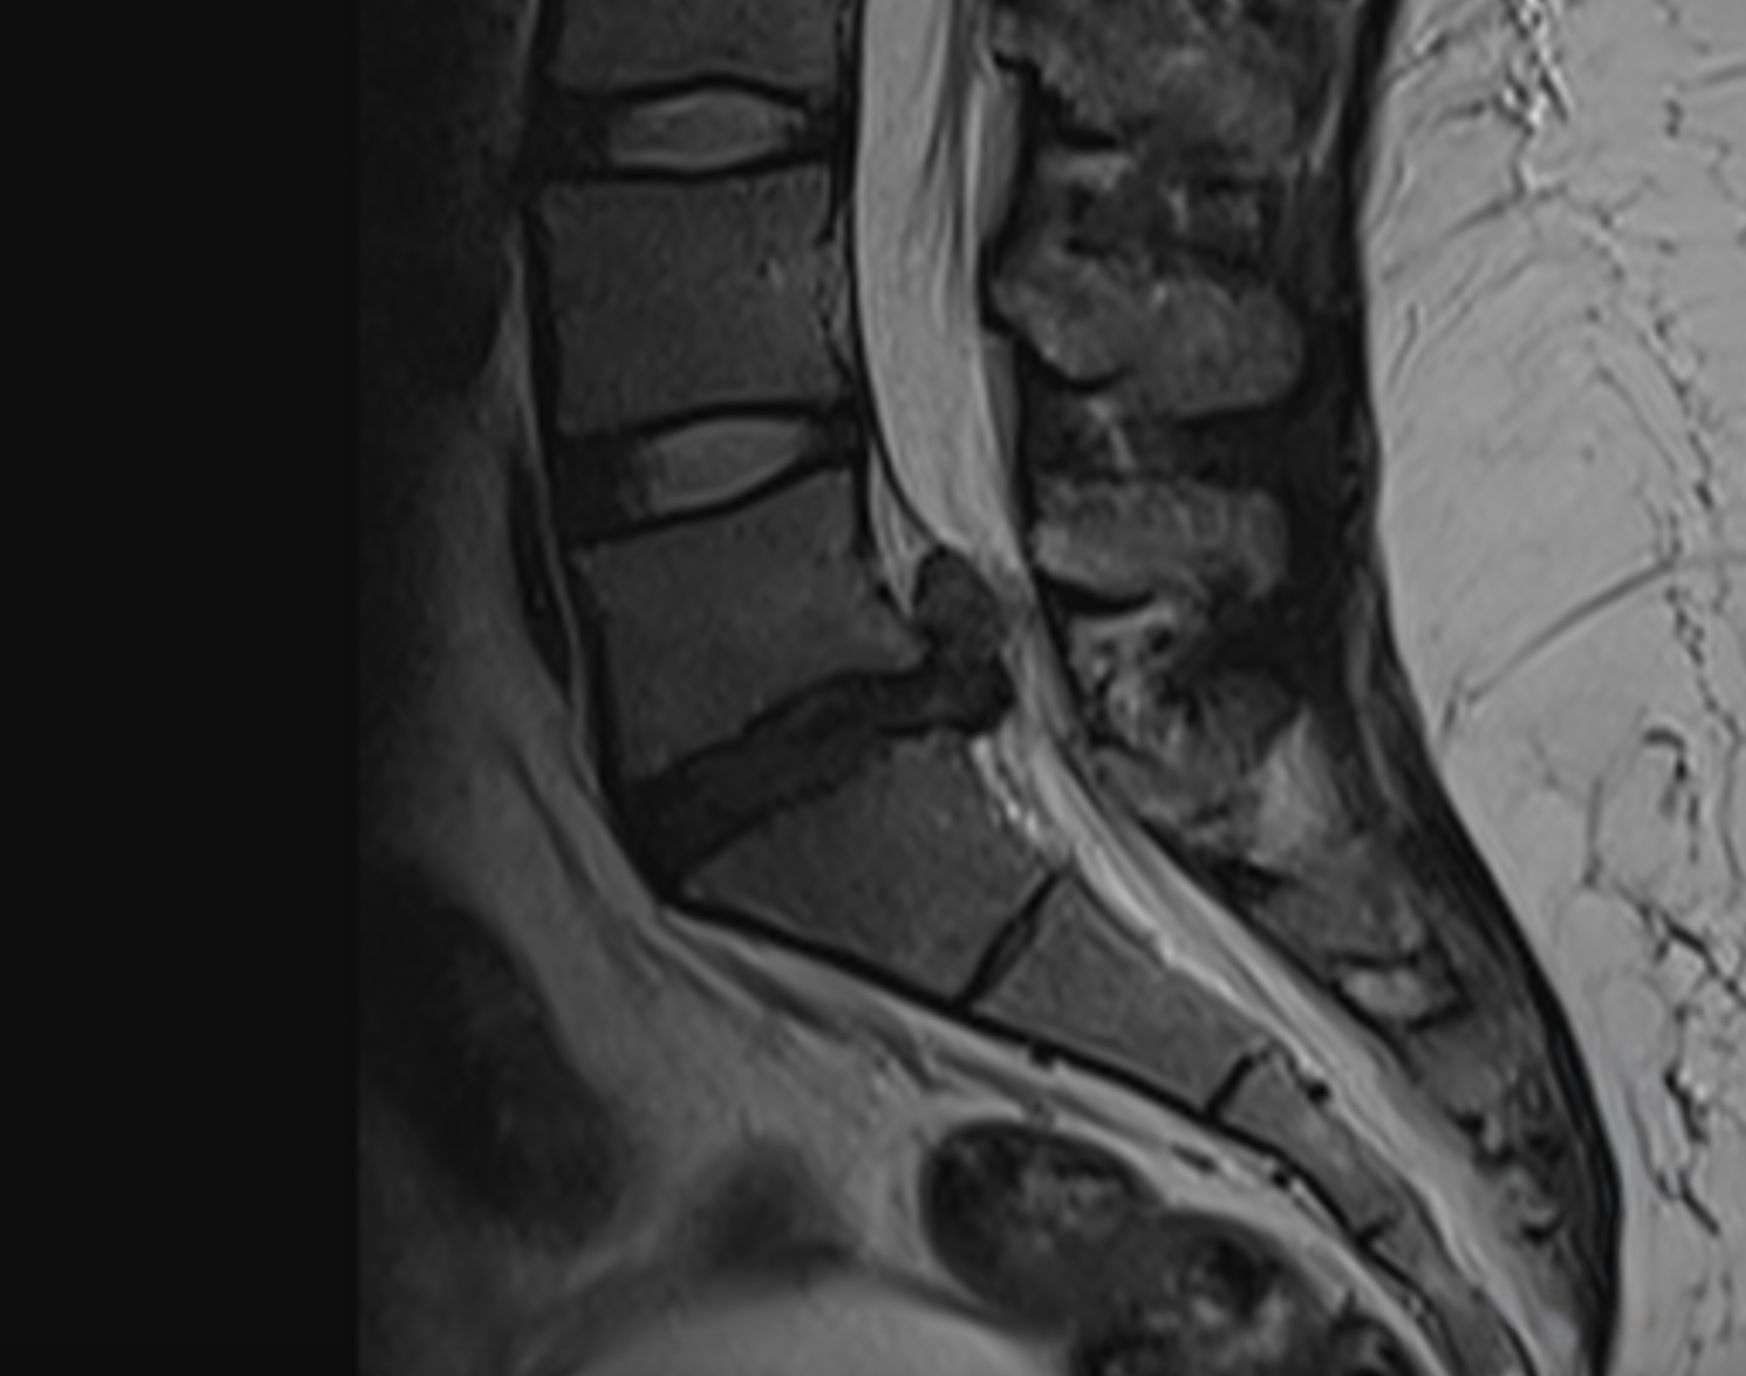

Cas clinique 1

Diagnostic

Patiente de 32 ans. Symptômes : Lombosciatique bilatérale invalidante, associée à des paresthésies et à une légère sensation de faiblesse musculaire lors de la dorsiflexion des pieds. Diagnostic : Hernie discale L5-S1 importante.